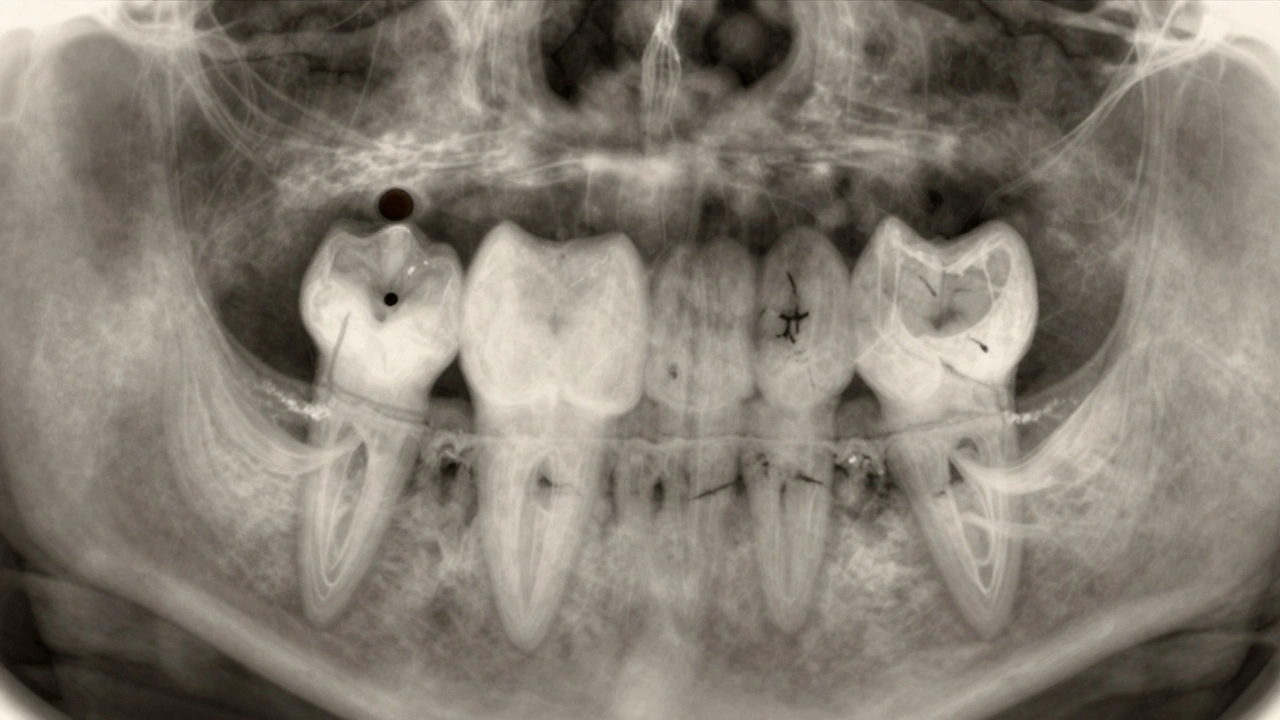

Na rentgenu se zubní kaz ukazuje jako tmavší skvrna nebo díra ve struktuře zubu. To znamená, že zde už není zdravá tvrdá tkáň - zubní sklovina nebo zubní dentin - ale místo ní je prázdný prostor, který rentgenové paprsky procházejí snadněji. A proto se na snímku zobrazí jako tmavší oblast. Ne každá tmavá skvrna je ale kaz. Někdy to může být jen zbytky plomby, kávová barva nebo zubní kámen. Proto dentista nejen dívá na tmavé místo, ale zkoumá jeho tvar, velikost, polohu a jak se chová vůči okolní tkáni.

Co vidíte na rentgenovém snímku, když je zubní kaz

Když se podíváte na rentgen zubu s kazem, vypadá to jako tmavý oblouček nebo kruh na bokové straně zubu, často mezi dvěma zuby. To je tzv. mezizubní kaz, který se rozvíjí tam, kde kartáček nedosáhne. Na předních zubech se kaz může objevit jako tmavá linie u zubního hranolu, kde se sklovina začíná rozpadat. Pokud je kaz hluboký, uvidíte, jak tmavá oblast proniká až k zubnímu nervu - to je známka pokročilého poškození.

Na rentgenu se také vidí, jak se kaz šíří pod plombou. Pokud je plomba na zubě, ale pod ní je tmavá oblast, znamená to, že se pod ní opět začal vyvíjet kaz. To se často stává, když plomba nebyla správně přilepená nebo se při žvýkání uvolnila. Dentista to vidí hned - a ví, že je potřeba plombu vyměnit a kaz odstranit, jinak se poškození rozšíří do zubního nervu.